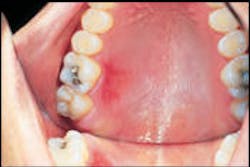

Oral examination revealed a red lesion on the hard palate of a 26-year-old male receiving routine dental treatment.

Examination of the head and neck regions revealed no unusual or significant findings. Oral examination revealed one superficial erosion on the palatal mucosa adjacent to molars. The lesion measured approximately two centimeters by one centimeter in diameter (see photo). The lesion appeared red in color. Further oral examination revealed no other oral lesions present.

Thermal burns caused by hot foods are found most often on the tissues of the hard palate and posterior buccal mucosa. Thermal burns caused by hot liquids are likely to involve the tongue and soft palate. The thermal burn typically appears as an erythematous, superficial erosion. The size and depth of the lesion vary, depending on the type of food, the temperature of the food, and the length of time the food was in contact with the oral tissues.